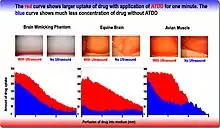

Due to their ability to oscillate with exposure to low-frequency ultrasound, microbubbles have been used as contrast agents in order to visualize tissues in which the microbubbles have permeated.[44] However, when these microspheres are exposed to higher pressure ultrasound, they can rupture, which could be beneficial for drug delivery purposes.[44] Through SDT, these microbubbles could be selectively bursted at the tumor microenvironment in order to decrease systemic levels of the encapsulated drug and increase therapeutic efficacy. When applying SDT, the increase in acoustic pressure leads to the inertial cavitation, or collapse of the microbubble and local release of the cargo within. The inertial cavitation of the microbubbles when exposed to SDT is also referred to as ultrasound mediated microbubble destruction (UMMD).[45] The shell of microbubbles can be decorated with different components, including polymers, lipids, or proteins depending on their intended purpose.[44] Microbubbles have also been used for the localized release of attached cargo. This cargo is typically chemotherapeutics, antibiotics, or genes.[12] Different drugs can be directly loaded into the microbubble with methods such as conjugation and nanoparticle, liposome loading, and genes. The combination of genes and SDT is referred to as sonotransfection.[12] Examples of outer shell modifications can be seen in a study by McEwan et al. which found that lipid microbubbles showed reduced stability when sonosensitizers were added to their shells.[44] However, attaching the polymer poly lactic-co-glycolic acid (PLGA) to the shell resulted in increased stability compared to the lipid microbubbles without losing other desirable properties such as targeted delivery and selective cytotoxicity.[44] In another study, McEwan et al. investigated the ability of microbubbles carrying oxygen to increase production of reactive oxygen species, which are a necessary component of SDT, in the hypoxic environment of many solid tumors.[46] These microbubbles were stabilized with lipids and a Rose Bengal sonosensitizer was attached to the surface to treat pancreatic cancer.[46] Their work showed that coupling oxygen-loaded microbubbles that are sensitive to ultrasound with sonosensitizing drugs could allow for increased drug activation at the desired target even if hypoxia is present. Examples of therapeutics that have been loaded into microbubbles are gemcitabine, paclitaxel nanoparticles, plasmid DNA and 2,2′-azobis[2-(2-imidazolin-2-yl)propane]dihydrochloride loaded liposomes.[47][45][48][49] Due to the targeting nature of the ligands connected to the microbubble, it allows for the controlled and specific targeting of the desired tissue for treatment. Another study performed by Nesbitt et al. has shown improved tumor reduction when gemcitabine was loaded into the microbubble and applied to a human pancreatic cancer xenograft model with SDT.[48]

- 1 2 3 Liao, Ai-Ho; Li, Ying-Kai; Lee, Wei-Jiunn; Wu, Ming-Fang; Liu, Hao-Li; Kuo, Min-Liang (1 November 2012). "Estimating the Delivery Efficiency of Drug-Loaded Microbubbles in Cancer Cells with Ultrasound and Bioluminescence Imaging". Ultrasound in Medicine & Biology. 38 (11): 1938–1948. doi:10.1016/j.ultrasmedbio.2012.07.013. ISSN 0301-5629. PMID 22929655.